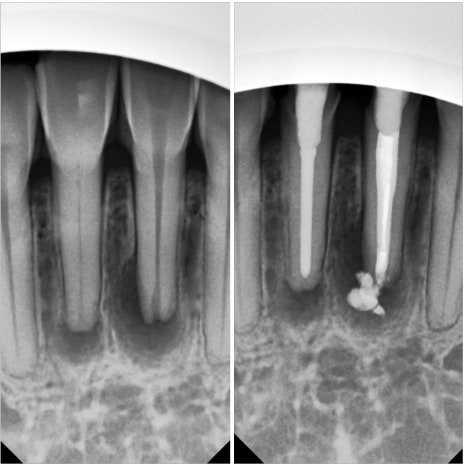

아래 앞니 신경치료 및 크라운 케이스

위 앞니 발치 즉시 임플란트, 크라운 케이스

분명히 신경치료가 필요한,

심지어는 발치가 필요한

충치 치아들이 있습니다.

그런 치아들까지

모두 레진으로 할 수 있는 것은

절대로 아니겠죠.